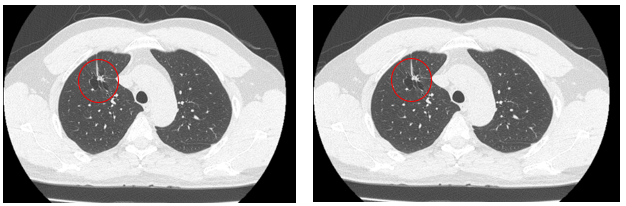

- Chụp cắt lớp vi tính ngực: Thùy trên phổi phải có nốt đặc kích thước 12x18mm, ngấm thuốc cản quang, bờ tua gai, có giãn phế nang kèm dải xẹp lân cận. Thùy trên có vài nốt nhỏ dưới màng phổi đường kính 3mm.

Hình 1: Hình ảnh chup cắt lớp vi tính ngực thấy khối u thùy trên phổi phải kích thước 12x18mm, bờ tua gai

Hình 2: Hình ảnh chup cắt lớp vi tính ngực thấy khối u thùy trên phổi phải kích thước 12x18 mm, bờ tua gai, ít thay đổi so với phim chụp

Siêu âm hạch vùng cổ: Hạch thượng đòn trái tăng kích thước 20mm, mất cấu trúc rốn hạch, phá vỡ xâm lấn vỏ bao

Nhận xét sau 3 tháng điều trị TKIs: Sau 03 tháng điều trị, khối u ổn định về kích thước tuy nhiên hạch thượng đòn tăng kích thước, chất chỉ điểm u tăng cao so với trước điều trị.